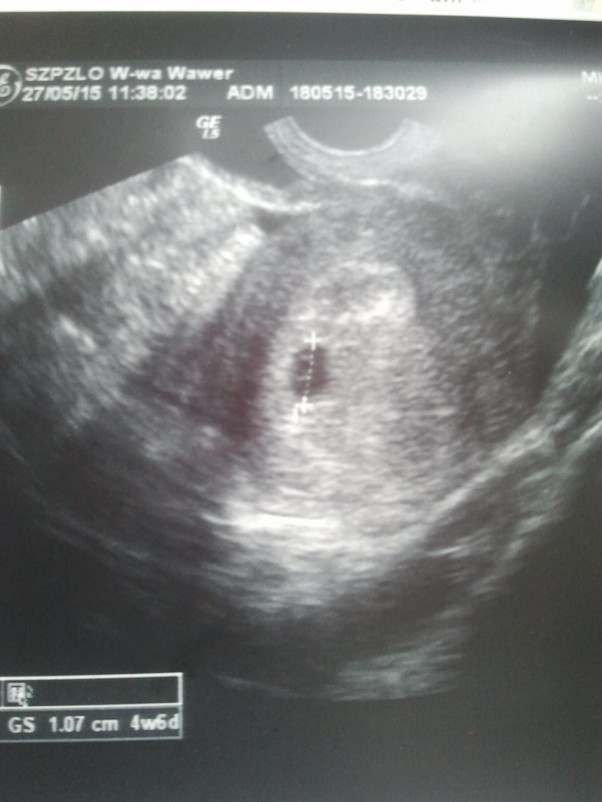

na kolejnej wizycie zobaczyłam migotanie serduszka i słyszałam tętno przez usg i komputer :) na poprzedniej wizycie tydzień wcześniej jeszcze było za wcześnie a na jeszcze wcześniej jeszcze tydzień wcześniej jeszcze nie było nic widać. ale test był pozytywny i lekarka dała skierowanie na badania z krwi, które też potwierdziły dzidziusia :)